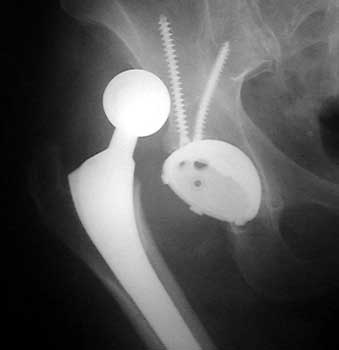

Dislocated femoral component related to non union of greater

trochanteric osteotomy. Post operative radiograph with constraining ring about

femoral head, which helps maintain head in cup. Greater trochanter resected.